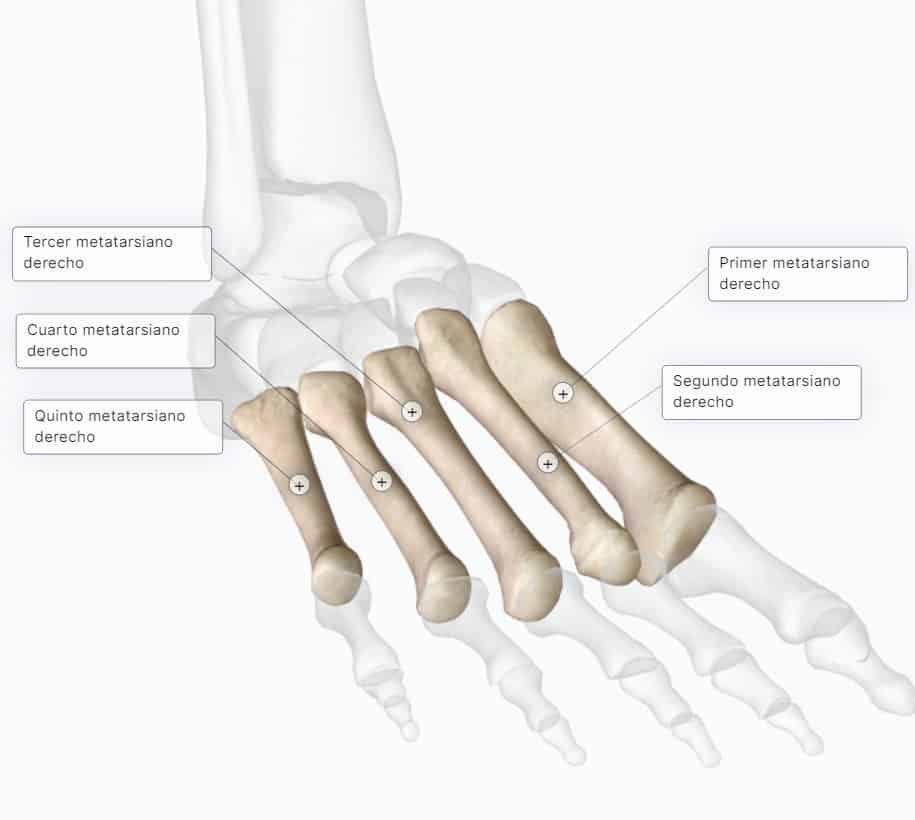

Primero hay que decir que los juanetes se clasifican en 3 clases de juanetes, o 3 patologías de las primeras cabezas metatarsianas. Las cabezas o las articulaciones tienen nombres: primera cabeza, segunda, tercera, cuarta y quinta cabeza metatarsiana, que son los metatarsianos del pie humano. No son los dedos, porque los dedos se llaman falanges.